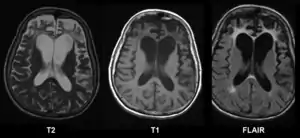

CT and MRI are most commonly used to observe the brain for cerebral atrophy. A CT scan takes cross sectional images of the brain using X-rays, while an MRI uses a magnetic field. With both measures, multiple images can be compared to see if there is a loss in brain volume over time.[20]

Cerebral atrophy can be hard to distinguish from hydrocephalus because both cerebral atrophy and hydrocephalus involve an increase in cerebrospinal fluid (CSF) volume. In cerebral atrophy, this increase in CSF volume comes as a result of the decrease in cortical volume. In hydrocephalus, the increase in volume happens due to the CSF itself.[20]